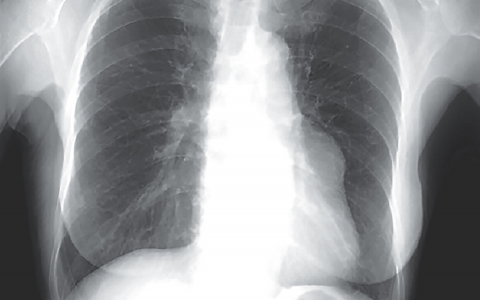

A 60-year-old man was admitted to the oncology floor for a urinary tract infection associated with mild confusion. His medical history is significant for metastatic non- small cell lung cancer, status post chemo- and radiation therapy, hypertension, and a deep venous thrombosis, for which he takes enoxaparin. Throughout the night, he is noted to have more shortness of breath and new-onset hypotension, and is urgently transferred to the ICU, where his vital signs are: temperature 38°C (100.4°F), heart rate 140 beats/min, respiratory rate 35 breaths/min, blood pressure 70/50 mm Hg, oxygen saturation 99% on a nonrebreather mask. Physical examination is notable for equal and reactive pupils, distended neck veins with supple neck, clear lungs, distant heart sounds, soft abdomen, cool extremities without edema, and confusion. Chest radiograph shows clear lungs and cardiomegaly. ECG shows sinus tachycardia with low voltage. Laboratory results are pending.

该患者有恶性心包积液,导致生理性填塞和阻塞性休克。首次检查他时,最谨慎的做法是进行快速超声评估以进行休克和低血压 (RUSH) 检查,并在看到积液后提供静脉推注。届时,需要根据他的临床状况决定在床边或导管室引流积液。用于急性呼吸困难和休克的床边超声检查是重症医师的重要工具。这将有助于迅速缩小鉴别诊断范围并改进决策。